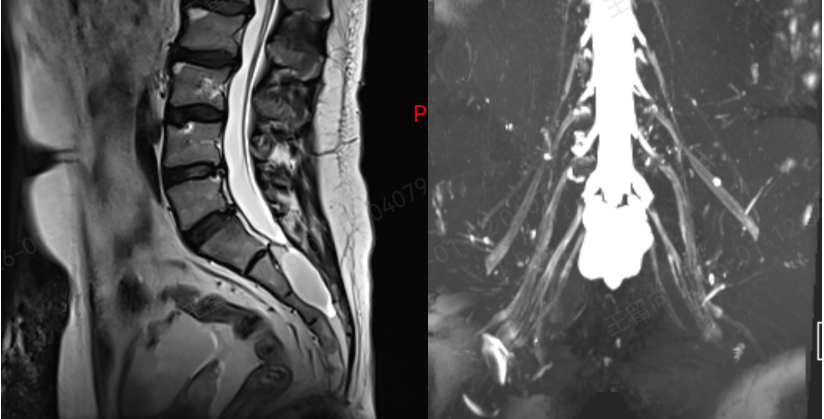

接诊后,孙红山副主任医师团队立即为刘先生展开全面评估,结合详细问诊和复查的核磁共振(MRI)结果,明确诊断其疼痛的根源正是骶管囊肿。

作为诊断和鉴别骶管囊肿的 “金标准”,MRI 虽能清晰显示病灶,但由于大众对这种疾病普遍缺乏正确认识,临床中误诊漏诊情况时有发生。

而刘先生的疼痛,正是因为囊肿内的神经根被牵拉,同时邻近神经根受到挤压,才导致了持续性的腰骶部疼痛,并非简单的腰肌劳损。